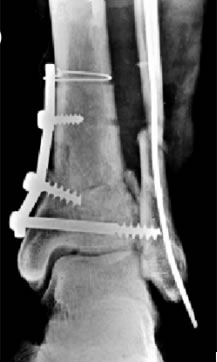

Ankle

![]() source: Christus Southern New Mexico |